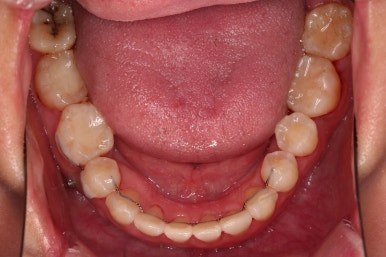

4. 마무리

위아래 좌우 치아가 없는 위치가 모두 달랐지만 교합도 잘 구성했고요.

아무래도 좌우 치아 크기들이 다르다 보니(뽑은 치아가 다르니) 중앙선은 100% 일직선은 안맞더라도 매우 정상 범주로 마무리를 할 수 있었습니다.

특히 어금니에 보이던 충치도 깔끔하게 마무리 했고요.

이제 부산교정치과 전후 비교해 보겠습니다.

치아배열, 틈새, 교합, 중앙선, 입매, 심지어 충치까지 깔끔히 잘 마무리 되었습니다.